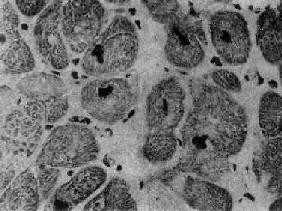

肥厚性心肌病

图8-37 肥厚性心肌病

心肌细胞排列紊乱 ×180(原放大)(采自Edwards)

镜下,心肌细胞显著肥大,核大而浓染(图8-36),核周有亮区包围,组织化学染色证明为糖原堆积,具有一定的诊断意义。心肌细胞排列紊乱较其它型心肌病为甚,而且常呈旋涡状或缠绕呈簇状排列(图8-37),细胞内肌原纤维不呈平行排列,而是向各个方向、互相交错排列。常有间质纤维化灶形成,但以内膜纤维化,尤其位于主动脉瓣下区的内膜纤维化为突出。位于肥厚的室间隔内的冠状动脉分支管壁常有增厚现象。